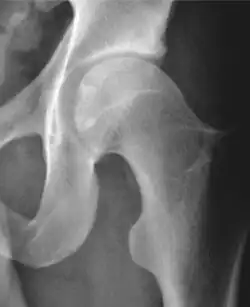

Projectional radiography ("X-ray") is often considered first line for FAI.[10] Anterior-posterior pelvis and a lateral image of the hip in question should be attained.[10] A 45-degree Dunn view is also recommended.[10][19]